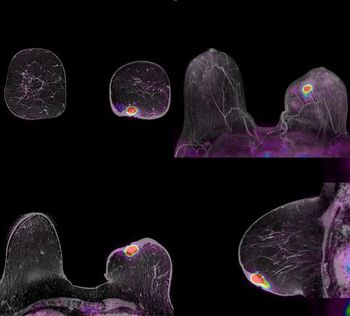

A new approach that detects breast cancer vasculature is making an appearance at the 2010 RSNA meeting. The method, called high spectral and spatial resolution, or HiSS, uses water to detect tumor blood vessels without contrast.